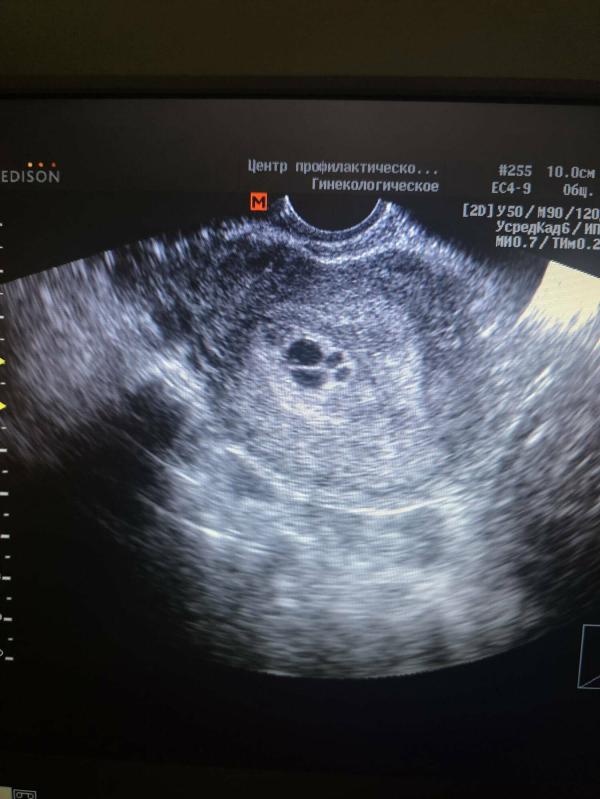

Все плохо))) по узи сказали что плхоже на пузырный занос😭😭😭

ну да похоже ((